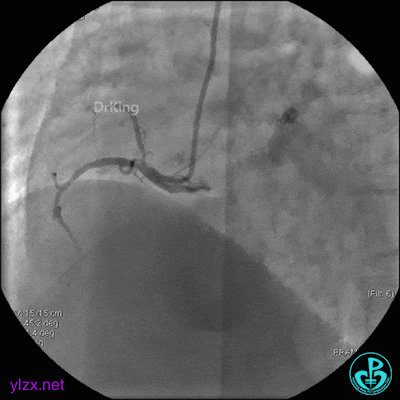

6 二次治疗

1周后复查造影,见粗大前降支3级血流,近端严重狭窄伴管壁严重钙化影,病变累及前降支开口。

球囊扩张后前降支中段植入支架。

前降支近端串联植入支架,前降支开口支架精确定位。

支架内非顺应性球囊后扩张。

最后造影结果显示前降支3级血流,支架膨胀尚可。